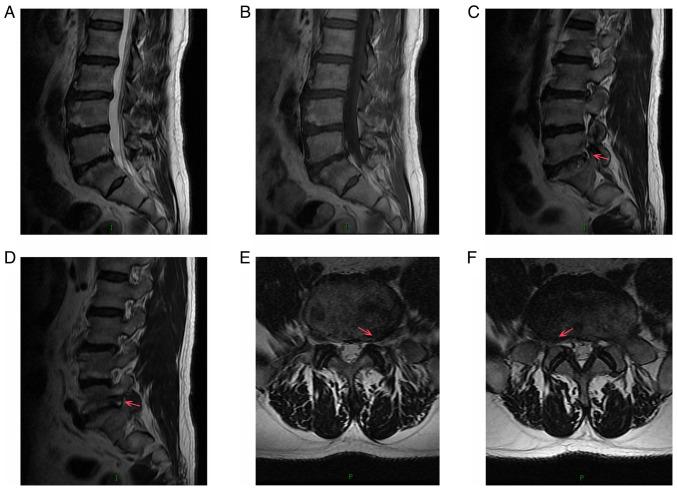

Spinal gout is a relatively rare disease characterized by significant clinical symptoms. In the current study, the first case of spinal gout with tophus in the intervertebral foramen, which perfectly mimicked degenerative lumbar disc disorders, was presented. The patient was a 57-year-old man with a medical history of gout who had suffered from progressive neurological deterioration for the last 12 months. Imaging examination revealed bilateral stenosis in the L5/S1 intervertebral foramen, mimicking degenerative lumbar disc disease. Nerve root radiculography and blocking were performed and the neurological symptoms were completely relieved. Open surgery was further performed and unexpectedly, the intra-operative findings were amorphous chalky white lesions. Histopathology confirmed the diagnosis of spinal gout. After surgery, the patient was prescribed a medication and achieved complete remission of clinical symptoms. No deterioration was found at the 1-year follow-up. To the best of our knowledge, this is the first report of spinal gout tophus in intervertebral foramen in the literature. It was concluded that, although intraspinal tophaceous gout is relatively rare, orthopedic surgeons should take it into consideration as a differential diagnosis, particularly if the patient has a medical history of gout. Early diagnosis and timely medical management may possibly be able to avoid neurological compromise and the need for surgery.

脊柱痛风是一种相对罕见的疾病,具有明显的临床症状。在本研究中,报告了首例椎间孔有痛风石的脊柱痛风病例,该病例酷似退行性腰椎间盘疾病。患者为一名57岁男性,有痛风病史,在过去12个月中出现进行性神经功能恶化。影像学检查显示L5/S1椎间孔双侧狭窄,类似退行性腰椎间盘疾病。进行了神经根造影和阻滞,神经症状完全缓解。进一步进行了开放手术,术中意外发现为无定形的灰白色病变。组织病理学确诊为脊柱痛风。术后给患者开了药,临床症状完全缓解。1年随访未发现病情恶化。据我们所知,这是文献中首例关于椎间孔脊柱痛风石的报告。结论是,尽管脊髓痛风石相对罕见,但骨科医生应将其作为鉴别诊断考虑,特别是如果患者有痛风病史。早期诊断和及时的医疗管理可能能够避免神经功能损害和手术需求。